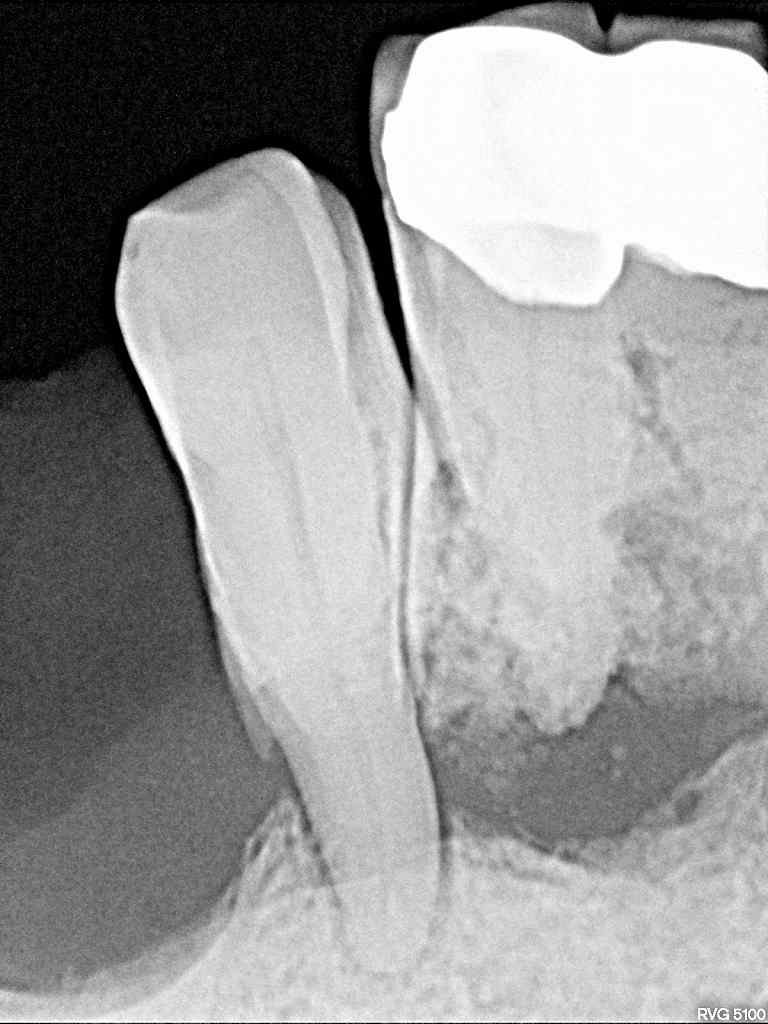

右側は右下の3番部だけでもっています

後の歯はすべて骨内に存在していません

左下も3番部だけで持っていました